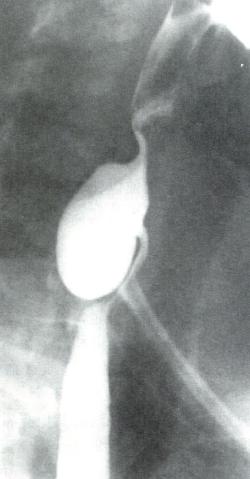

为诊断Zenker憩室的首选检查(图2.6)。

图2.6 Zenker憩室的X线表现。憩室囊位于食管后方。